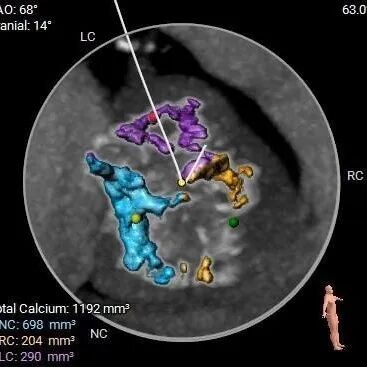

重度钙化,HU 850积分1192mm3

•功能型二叶瓣,瓣叶增厚,R-L间有钙化嵴,重度钙化,钙化于各窦内延伸分布,无冠窦内钙化居多,左、右冠窦下各有部分钙化向LVOT延伸;LVOT接近直筒型,

•左、右冠高度可,切线位测量,左窦瓣叶略长于左冠开口下缘;左主干分叉附近可见钙化分布,

•瓦氏窦增宽,STJ及升主扩张,

•主动脉瓣水平夹角约74°,严重横位心,主动脉弓宽度角度可,弓顶部有钙化分布,

•股-髂动脉走行稍迂曲,内径可,右侧股动脉穿刺点偏下位置有钙化块分布,腹主-髂总大量附壁钙化,

•推荐18mm球囊预扩,预装AV29瓣膜。